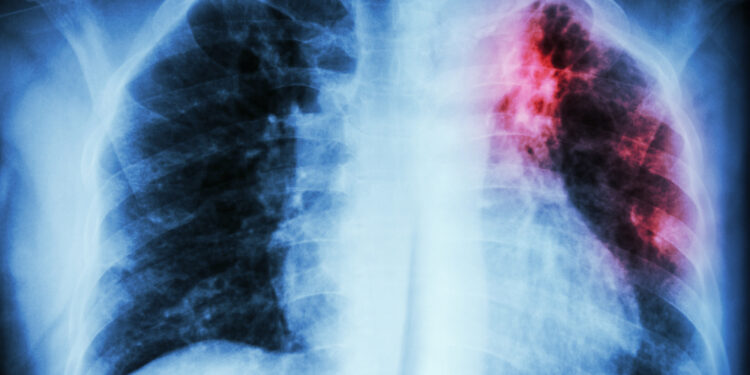

- Krūtinės ląstos rentgenograma

- Kompiuterinė tomografija (KT)